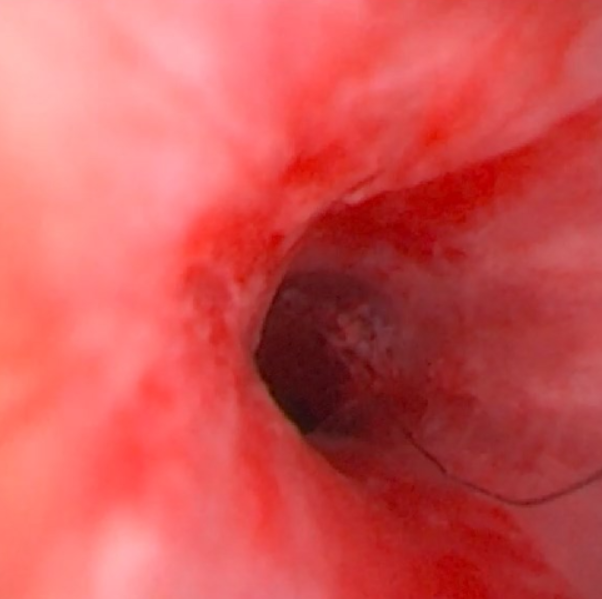

Bladder 안과 trigone(방광 삼각부), ureter가 열리는 부위까지 잘 보이도록 한 상태에서, 작은 카메라인 cystoscope(방광경)을 절개창을 통해 넣어 bladder 안쪽 점막과 proximal urethra(방광 쪽 요도)를 자세히 관찰했습니다.

이 과정에서 눈에 잘 안 띄는 작은 결석과 동반된 염증·폴립 같은 병변이 있는지도 함께 확인했습니다.

또한 결석이 urethra 쪽으로 떨어졌을 가능성에 대비해, urethral catheter를 넣고 방광 쪽으로 물을 흘려 보내는 flushing을 여러 번 시행하여, urethra 안에 남아 있을 수 있는 결석까지 최대한 씻어 내도록 했습니다.

결석 제거가 끝난 뒤에는 방광경으로 다시 한 번 bladder 안 전체를 확인해 남아 있는 결석이 없는지 꼼꼼히 검사했습니다.

struvite, urate, cystine 일부는 특수 식이와 약물로 녹이는 것이 가능하나 Surgical cystotomy는 가장 전통적이고 많이 시행되는 방법으로 bladder를 여는 수술을 통해 결석을 모두 꺼내고 수술 중에는 cystoscope(방광경)을 이용해 bladder 안쪽 점막과 urethra 입구 근처까지 직접 보면서, 눈에 잘 보이지 않는 작은 결석이나 염증, 종괴가 남아 있지 않은지 확인하는 과정이 매우 중요합니다.

또한 urethral flushing(요도 플러싱)을 반복해서 시행해 urethra 안에 숨은 작은 결석까지 최대한 씻어 내야, 수술 후 요도 폐색이나 결석 재발 위험을 줄일 수 있습니다.